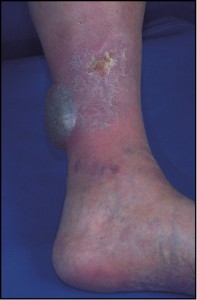

El melanoma se presenta predominantemente en adultos y más de 50% de los casos aparecen en áreas de la piel que son aparentemente normales. Entre los primeros signos en el nevo que indican cambios malignos están una coloración más oscura o variable, picazón, un aumento en el tamaño o el surgimiento de formaciones satélites. La ulceración o hemorragia son signos tardíos. El melanoma en mujeres se presenta con mayor frecuencia en las extremidades, y en hombres generalmente se presenta en el tronco, o en la cabeza y cuello, pero puede surgir en cualquier sitio de la superficie cutánea. La lesión típica es una mancha, generalmente asimétrica, mayor de 6 mm de diámetro, cuya coloración varía desde el marrón claro hasta el negro intenso, y generalmente irregular, con bordes dentados. Estas 4 características clínicas constituyen la denominada regla ABCD del melanoma (A: asimetría; B: bordes irregulares; C: color intenso; y D: diámetro mayor de 6 mm). Sin embargo, estos criterios también pueden observarse en lesiones melanocíticas benignas, así como hay melanomas que no las cumplen, por lo que no constituyen criterios diagnósticos absolutos. Clínicamente, se distinguen cuatro tipos de melanoma:

- Melanoma acrolentiginoso y mucoso. Es más frecuente en las personas de raza negra, apareciendo en palmas, plantas, región subungueal y en mucosas. Es una mácula amplia, de coloración desigual y bordes irregulares, en cuya superficie se pueden encontrar lesiones papulosas o tuberosas.

- Melanoma nodular. Aparece como una lesión papulosa o papulotuberosa, de tamaño variable y de superficie habitualmente negruzca, aunque puede ser incolora (melanoma amelanótico), que puede estar erosionada o ulcerada. Es la forma clínica de más rápido crecimiento y de peor pronóstico.